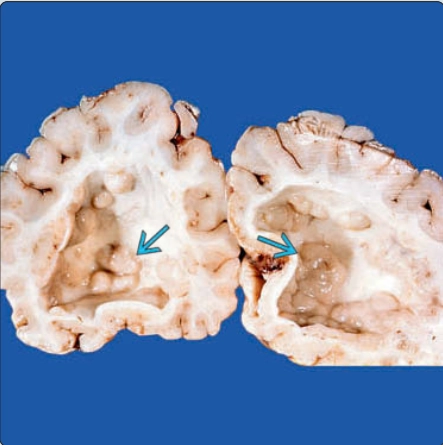

Giãn não thất thai nhi (Ventriculomegaly)